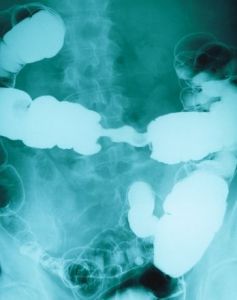

Что такое ИРРИГОСКОПИЯ?

Читайте об ирригоскопии ...